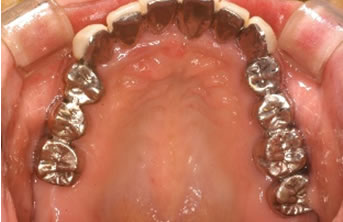

症例2

治療の特徴(患者Y様)

初診 2016年5月17日 / 経過 2018年7月2日

| 治療期間 | 2年2カ月 |

|---|---|

| 費用 | 保険内治療 |

| オペ費用 | 1ブロック約9,000円(3割負担) |

| 治療のデメリット | 歯内退縮が見られる。知覚過敏の症状が出ることがある。 |